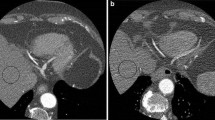

By calculating the tube-current-time settings equal to the patients weight in kilograms multiplied by four in milliampere seconds (group A2), an optimised dose distribution was achieved while retaining a nearly unimpaired diagnostic image quality. The average image quality according to the consensus assessment was 1.5±0.5 for group A1, 1.6±0.5 for group A2 and 1.7±0.7 for group B. No examination in any of the subgroups was rated as poor (score of 4) or non-diagnostic (score of 5) (Figs. 1, 2).

a Curved multiplanar reformation (MPR) of a male patient (50 kg, 1.74 m; group A1). Tube current-time settings: 400 mAseff, tube voltage 120 kV. b Same patient as in Fig. 1a with additionally added image noise (group A2). Simulated tube current-time settings: 200 mAseff, tube voltage 120 kV, simulated dose reduction of 50%